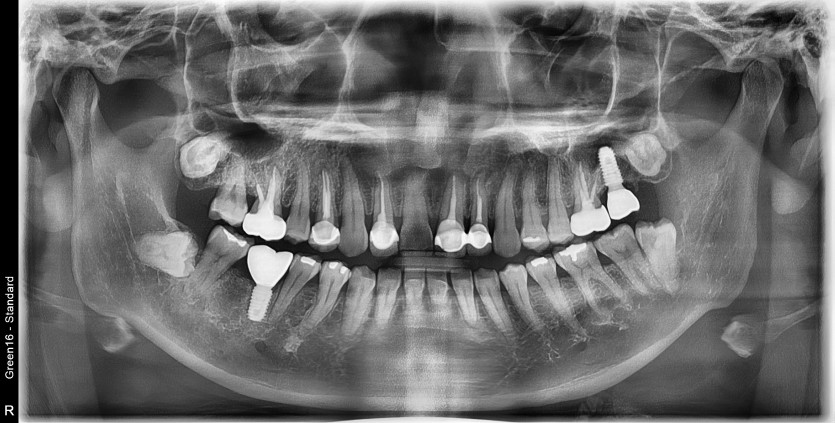

#38 사랑니 발치

구강 외과 전문의가 당일 발치했습니다.